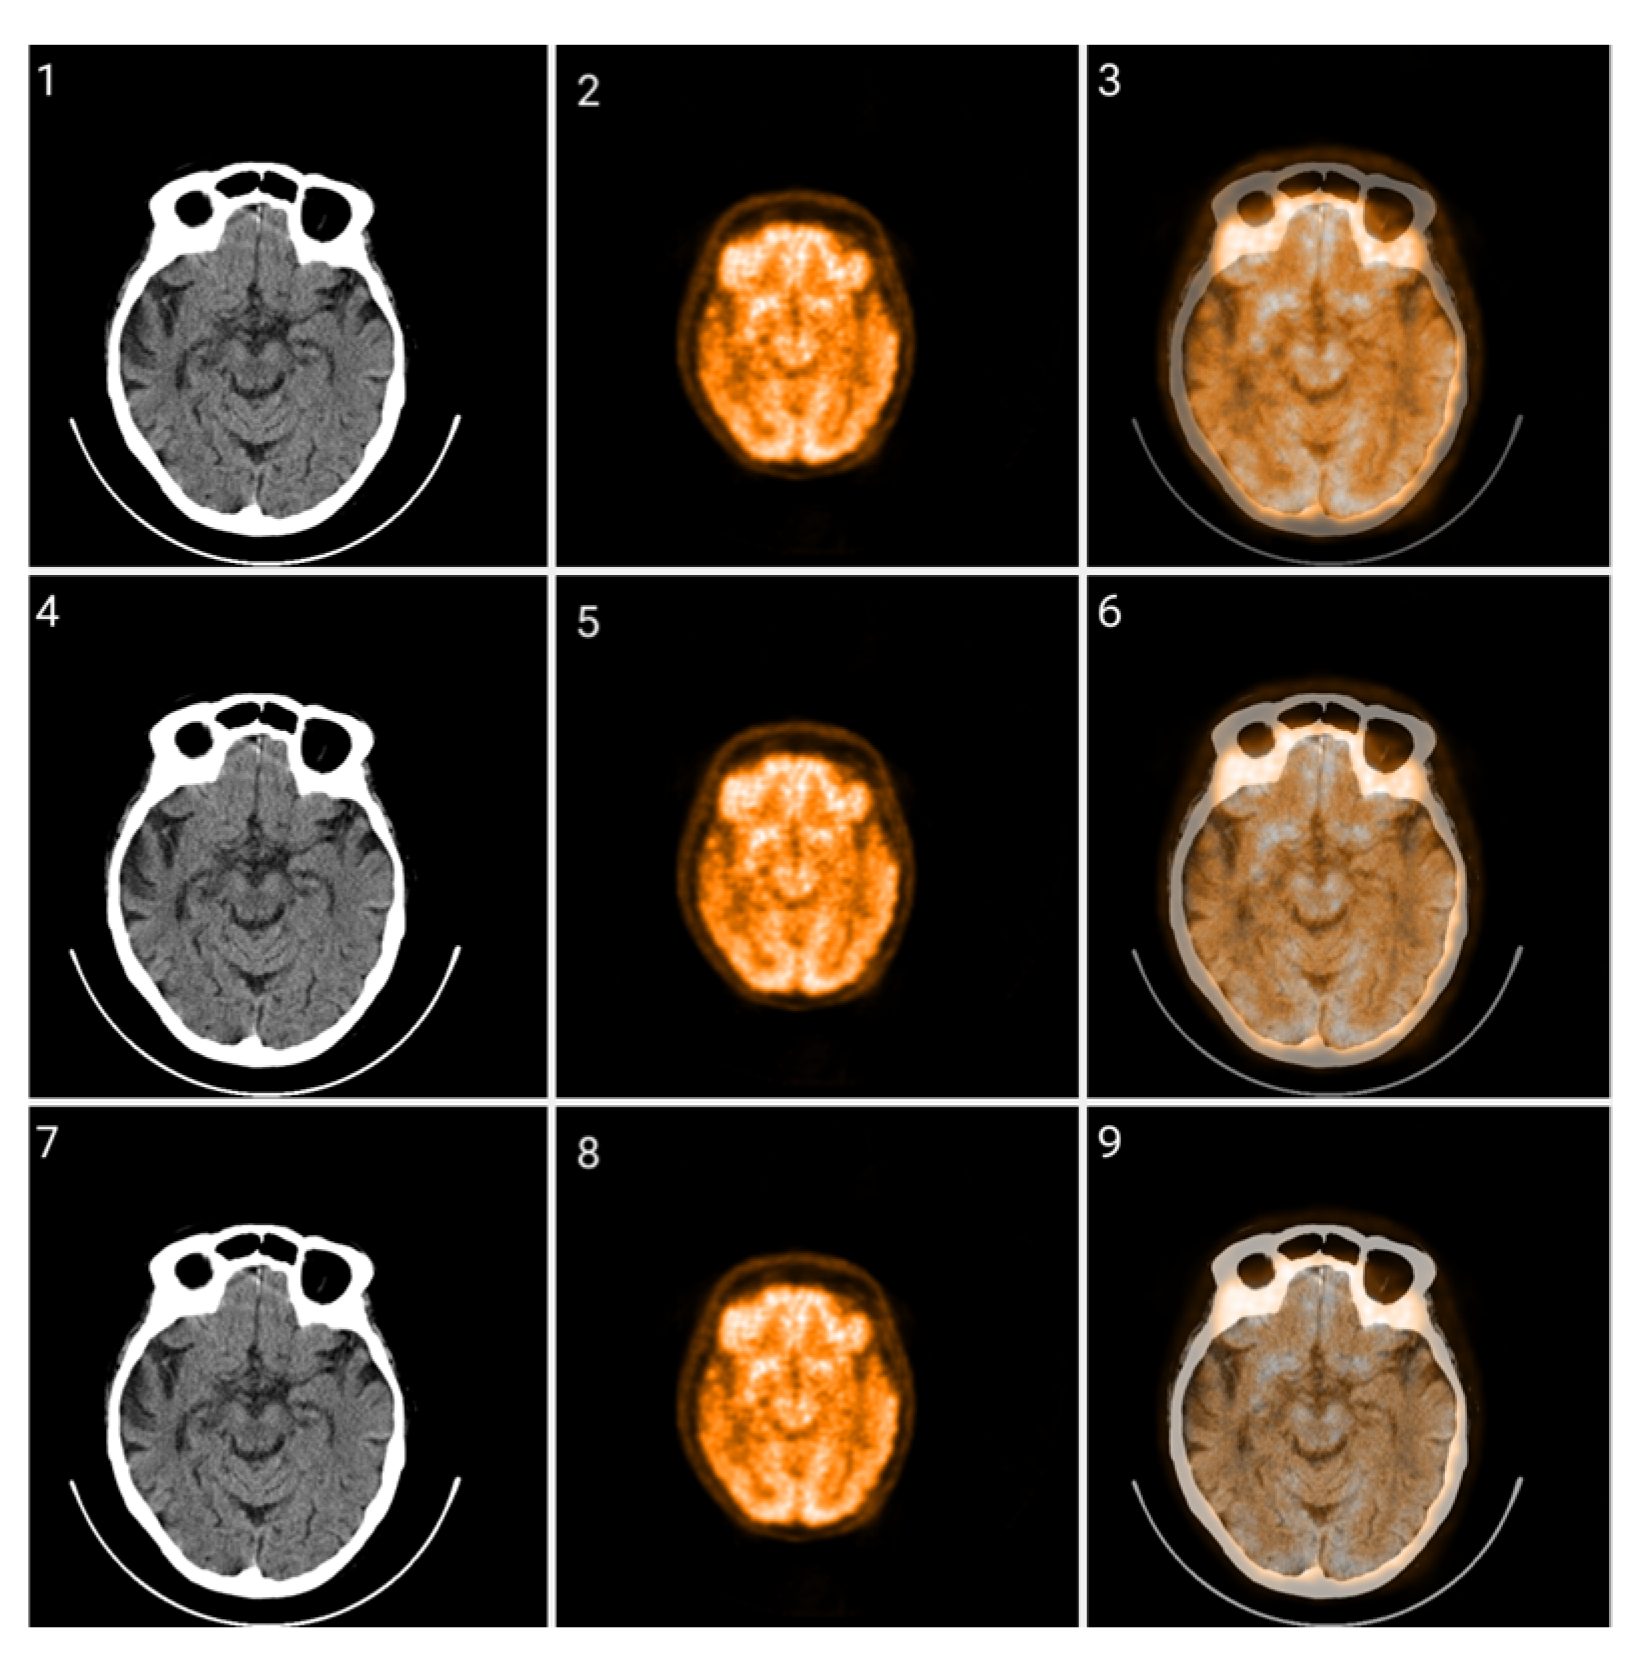

The proposed Colormap Folding method is carried out using only white, black, and colors. Gray shades are left out of the method because the classical CT grayscale images will be fused with PET images that have undergone colormap folding. The fusion was evaluated using different percentage ratios and the results are presented in Figure 12, Figure 13 and Figure 14 for different folds.

Figure 12.

Fusion of CT and PET images at different ratios. Images 1, 4, and 7 present a standard windowed CT image. Images 2, 5, and 8 present the corresponding PET image after Colormap Folding by 1 fold. Images 3, 6, and 9 present the results of fusing the CT and PET images at different ratios, 35%, 50%, 65% CT with 65%, 50%, 35% PET, respectively.